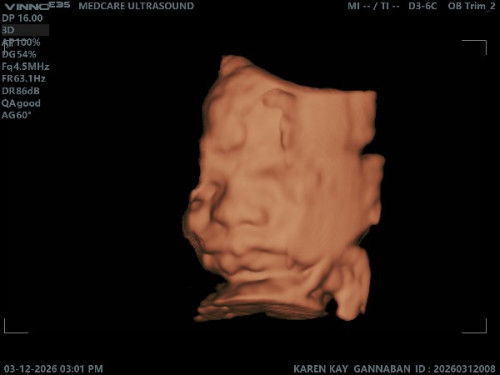

Hello sa mga mommies due June 2026!

Kaka-CAS ko lang po, thank God okay and complete naman si baby #2. ☺️ Last week nagpaOgtt naman ako at may 2 out of 3 test ako na nagspike up, kaya 1 week na rin akong puro healthy ang kinakain. Hehe Kayo, kmusta po sugar niyo? 🙏